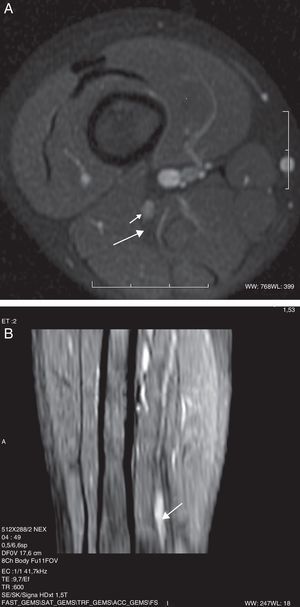

Entre las neuropatías de los nervios de las extremidades inferiores, las neuropatías posturales pueden ocurrir en una variedad de posiciones, las más descritas la de litotomía y la de sentado. Estas causas de lesión del nervio ciático son prevenibles y suelen ocurrir por descuido intraoperatorio, ya sea porque el paciente permanece demasiado tiempo en la misma postura, o por error en el posicionamiento. Esto ha tenido un alto impacto médico-legal29–31. En ambas posiciones, las mismas fuerzas que contribuyen a la lesión por estiramiento del grupo muscular de los isquiotibiales (por ejemplo, bíceps femoral), pueden generar el estiramiento del nervio ciático. Debido a que la posición afecta a la vez a ambos miembros, la afectación del nervio ciático puede ser bilateral. El trauma en el músculo piriforme genera espasmo o contractura muscular y, secundariamente, lesión del nervio por compresión y/o estiramiento32. Los hallazgos en RM, teniendo en cuenta el antecedente clínico, son muy sugestivos. Las imágenes muestran un engrosamiento fusiforme del nervio a su paso por la escotadura ciática, un foco de contusión en los músculos piriforme, cuadrado femoral y glúteo, así como cambios en los planos grasos adyacentes. La captación de contraste por estas estructuras se explica por el componente inflamatorio agudo del paquete vásculo-nervioso de la vaina neural, junto con la compresión muscular adyacente (fig. 4).

Niña de 13 años con antecedente de cirugía en posición sentada durante 8h. A) Secuencia IDEAL ponderada en T2 con saturación de la grasa en el plano coronal. Se observa un aumento de la señal y engrosamiento difuso de ambos nervios ciáticos, con predominio en el lado izquierdo (flecha). Se acompaña de edema de las partes blandas adyacentes en el lado izquierdo (asterisco). B) Reconstrucción MPR curva en el eje longitudinal del nervio.